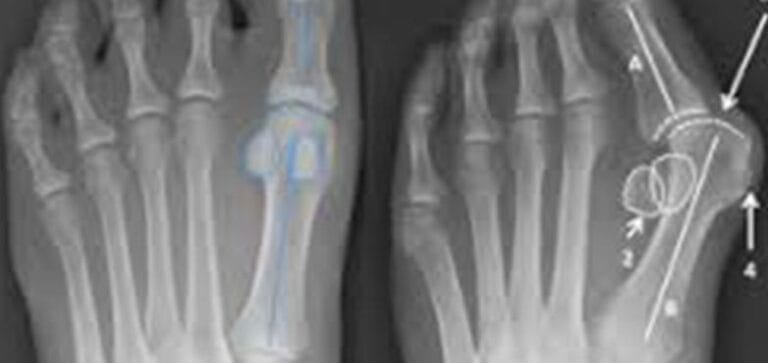

With a bunion, the big toe bends toward the second toe, creating a bump at the base of the toe. The bump can become red and swollen. Certain medical conditions, such as rheumatoid arthritis, can raise your risk for developing bunions. But the most common culprit is genetics. You probably inherited a foot shape and biomechanics that puts excess pressure on the big toe.